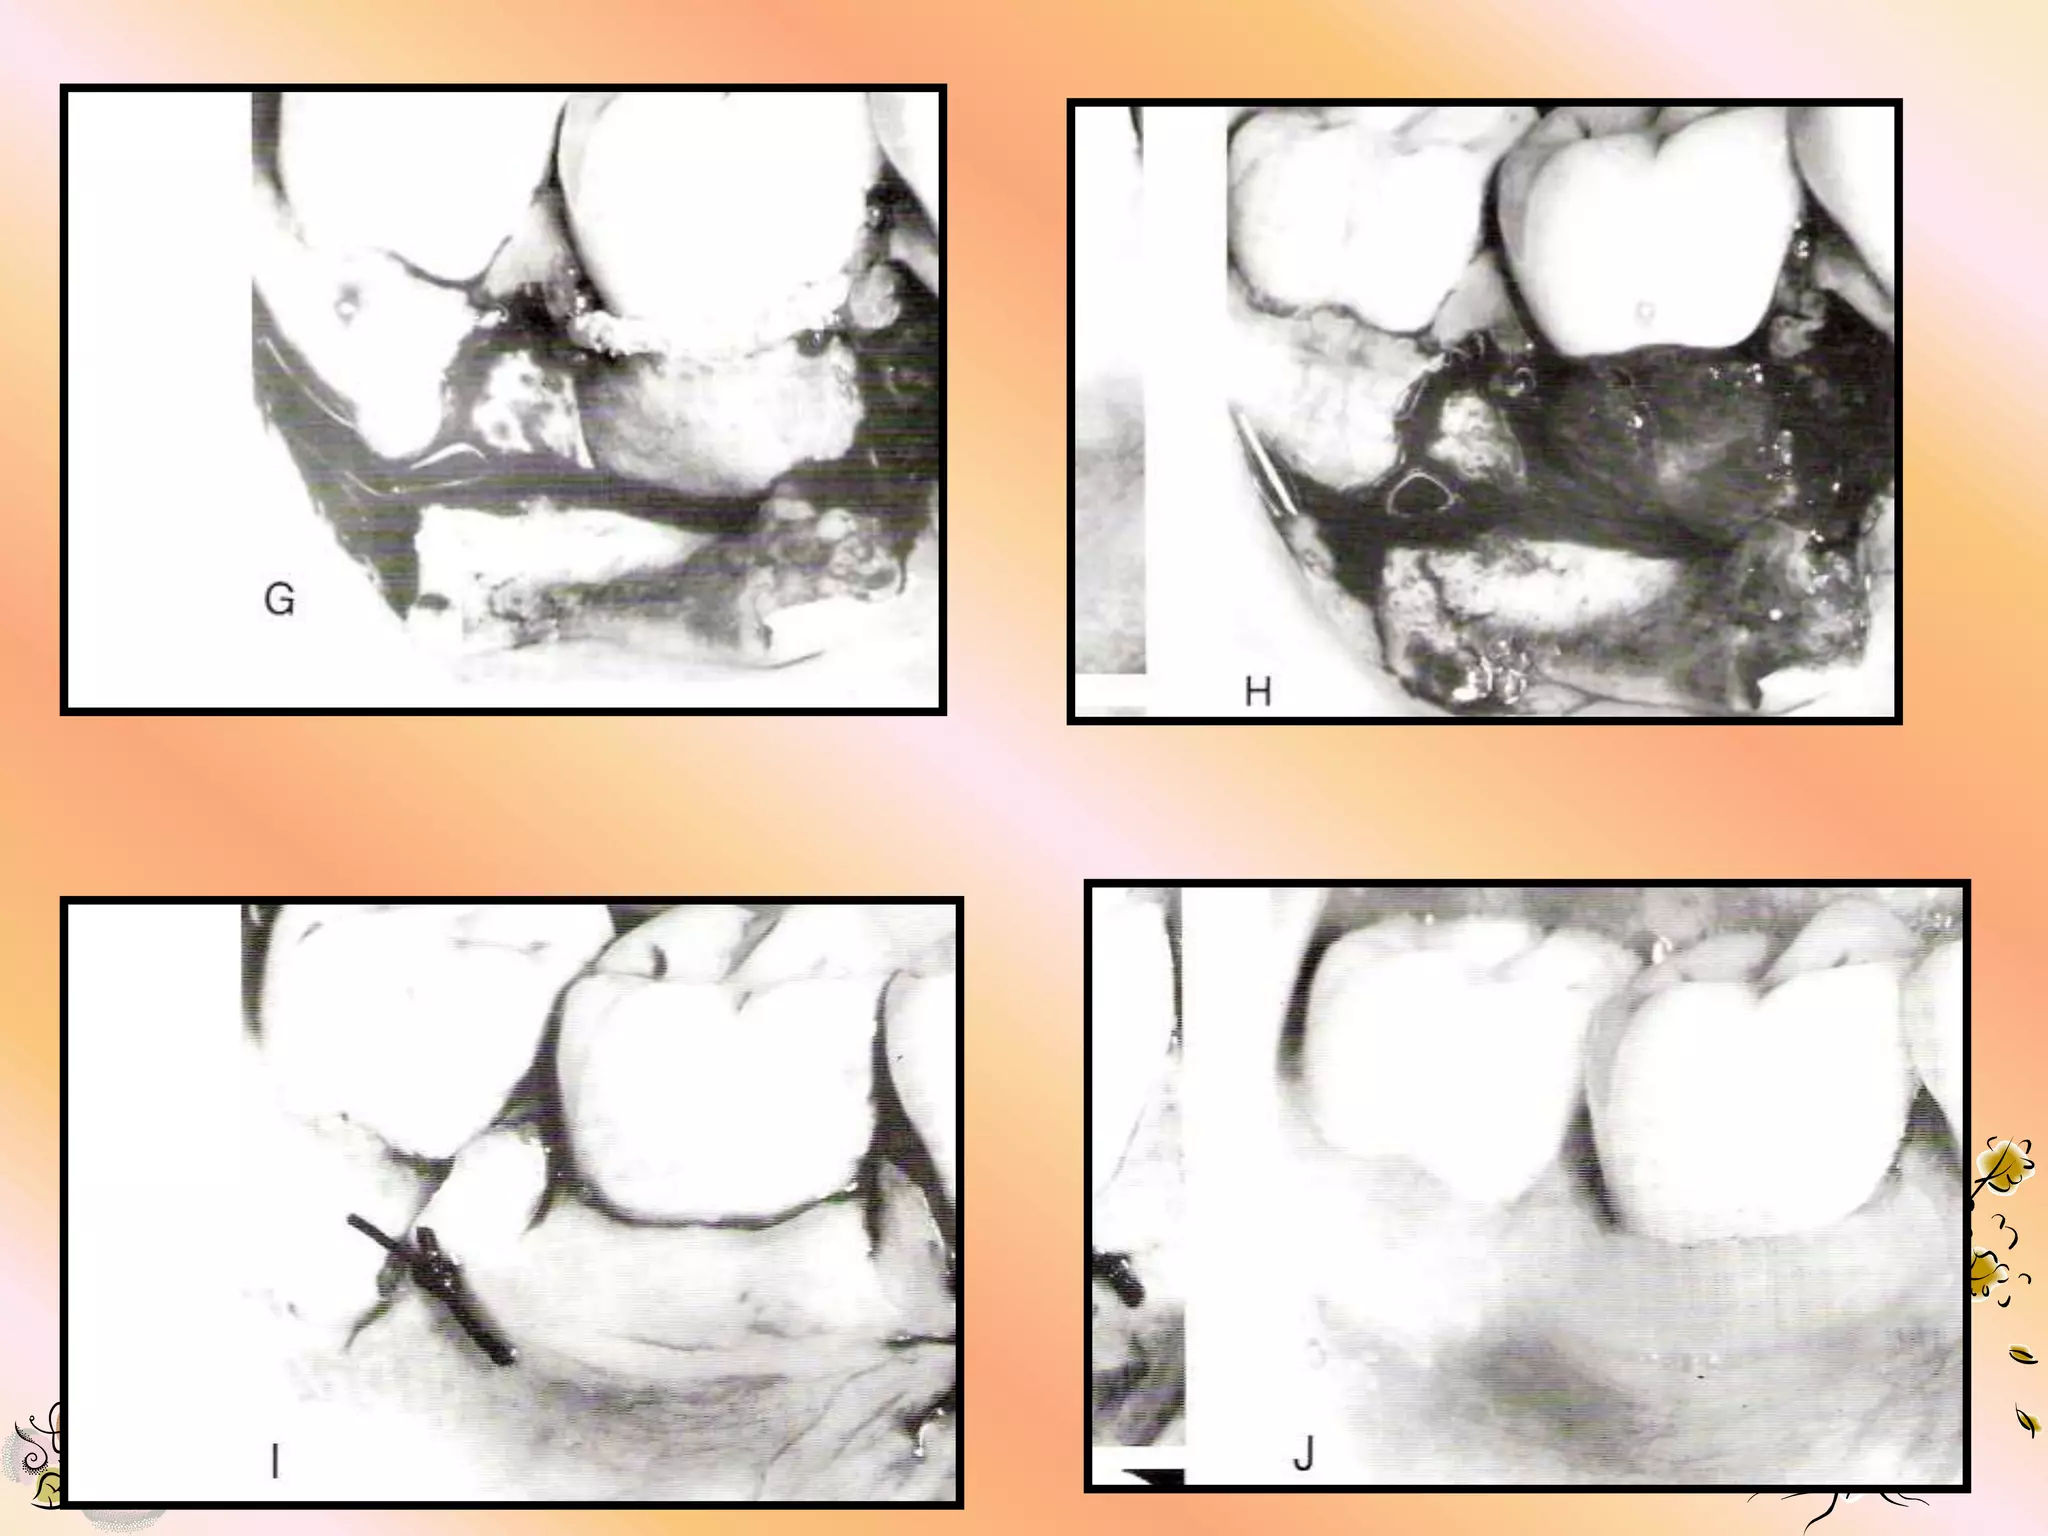

DEFECT PREPARATION

1. Degranulation of defect.

2. Scaling & root planning for removal of all

tooth deposits.

3. Decortification of bone for increased

vascularity & scratching of the PDL to

stimulate cell & vascular proliferation.

SELECTION & PLACEMENT OF

GORE-TEX PERIODONTAL

MATERIAL

1. Maintain sterility of material.

2. Choose a size that offers the most

ideal design for defect coverage.

3. Shape the material with scissors,

avoid leaving sharp edges.

4. Enough material should be left to permit lateral

& interproximal suturing while leaving at least 3

mm apical & lateral overextension of defect

margins.

5. Do not remove the open microstructure or

coronal portion of the material. It can be

trimmed on the lateral aspect.

6. The material should fit smoothly, avoiding folds,

overlaps & protrusions which may compromise the

overlying gingival tissue.